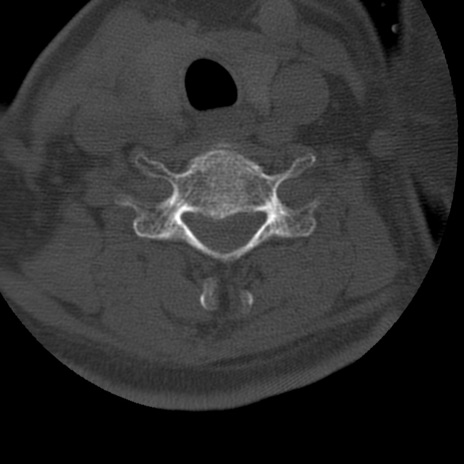

症例50 頚椎CT(横断像)

異常所見と診断は?

矢状断像